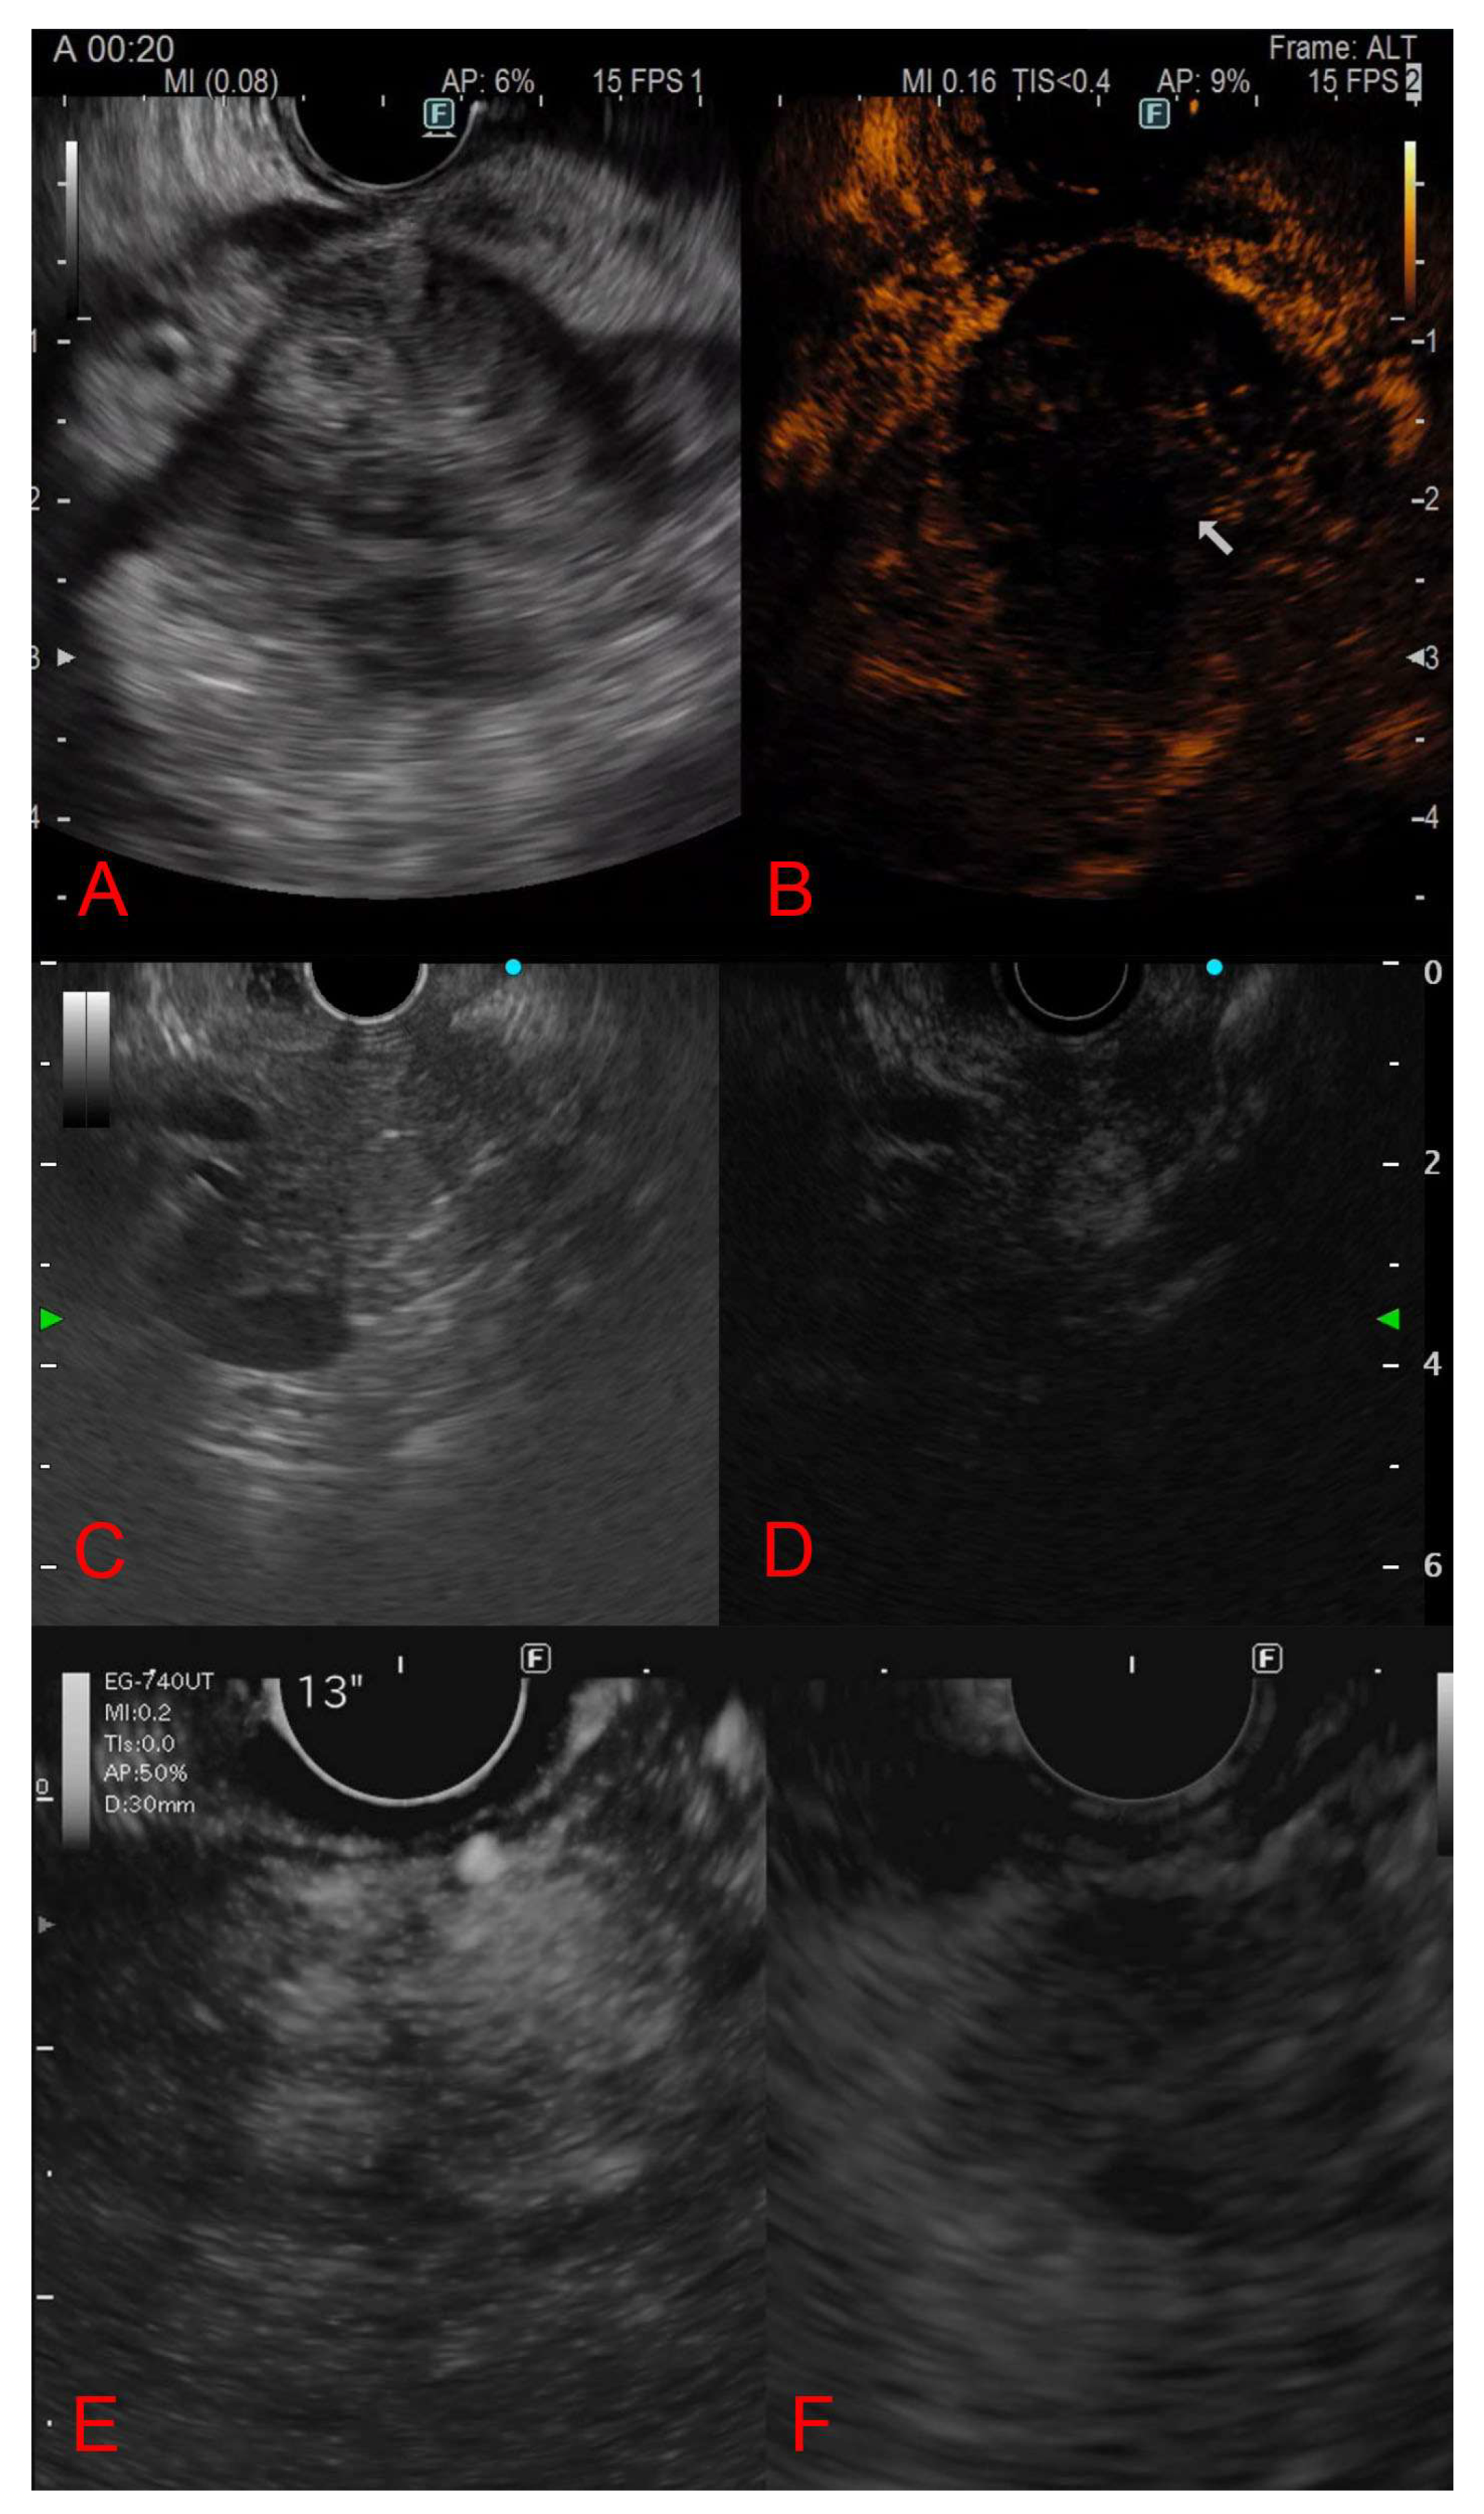

3.5. Contrast-Enhanced Endoscopic Ultrasound Features

3.6. Diagnostic Yield and Final Diagnostic Method